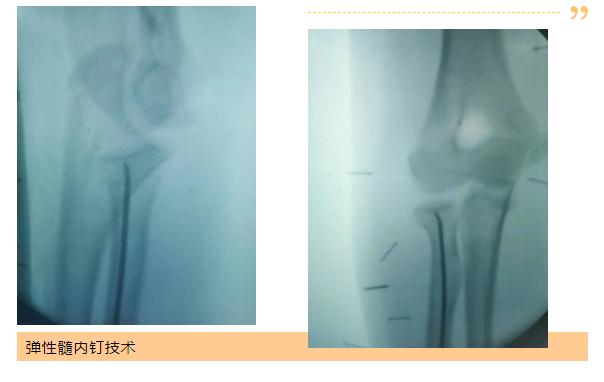

四肢损伤方面,科室运用中医优势技术,手法复位克氏针固定治疗桡骨远端骨折、儿童肱骨髁上骨折效果满意,免除二次手术的痛苦;运用损伤控制技术治疗骨科多发损伤,微创技术锁定接骨板和髓内钉固定治疗四肢骨折,对老年高龄髋部骨折采取微创手术治疗,能明显减少卧床并发症,同时应用中药内服活血化瘀、外敷通经止痛,促进消肿和快速康复;显微外科成功完成四指离断再植术、能熟练运用多种皮瓣、肌皮瓣修复外伤或疾病导致的组织缺损。